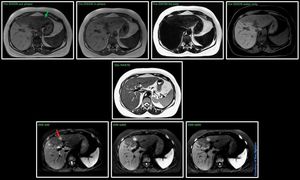

Is DWI needed for focal liver lesions imaging? @ Siemens 1.5T Aera The answer would be YES, always. Its powerful properties are insanely good for detect liver lesions. This is a fatty liver (green arrow), inside that fatty area there is also a lesion. with t1 dixon (in, out, fat and water) and t2w HASTE, extremely difficult to spot it. Then take a closer look at the DWI images (red arrow), easily seen in the eyes of a radiologist#Siemens_MRI #siemens #mri #fattyliver #dwi